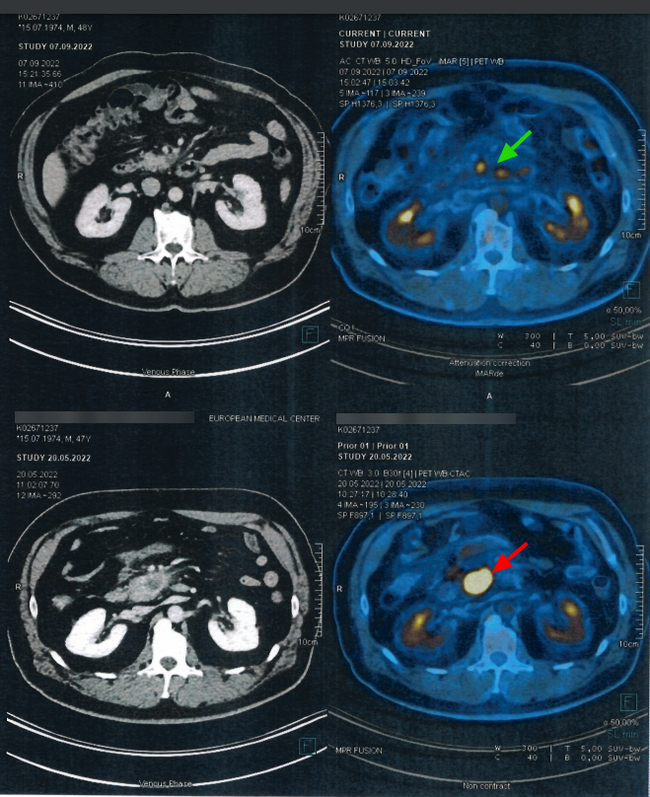

Невролог собрался отпускать домой с миром. Тут я вспомнила про шею! Напросилась сделать мне хотя бы рентген. И тут понеслось... Рентген выявил полное кольцо с левой стороны и полукольцо справа на первом шейном позвонке (Аномалия Киммерле). Ну, я-то знала - сужение есть, но никто тогда не сказал, что тенденция к полному зарастанию канала, и что этому есть научное название. По итогу рентгена невролог сказал сделать КТ с контрастов, чтоб посмотреть проходимость шейных вен. Как оказалось, слева всего лишь нитеподоный кровоток. Короче, почти нет сообщения с головой.

Заведующая неврологическим отделением внимательно смотрела снимки КТ много раз, дабы определиться, нужна ли консультация нейрохирурга. К этому времени я уже начиталась ужастиков в интернете о том, что следующая "станция" либо инсульт, либо внезапная потеря сознания. Во всех источниках рекомендовалась операция, которая связана с риском задеть эту нитеподобную вену при отрезании ненужного участка позвонка. Перспективы так себе.

И вот вердикт заведующей: "Консультация нейрохирурга не нужна. Кровоток же есть какой-то. Соседние сосуды компенсируют уже недостаток. Пейте таблетки Бетасерк, живите дальше. Выписывают домой"